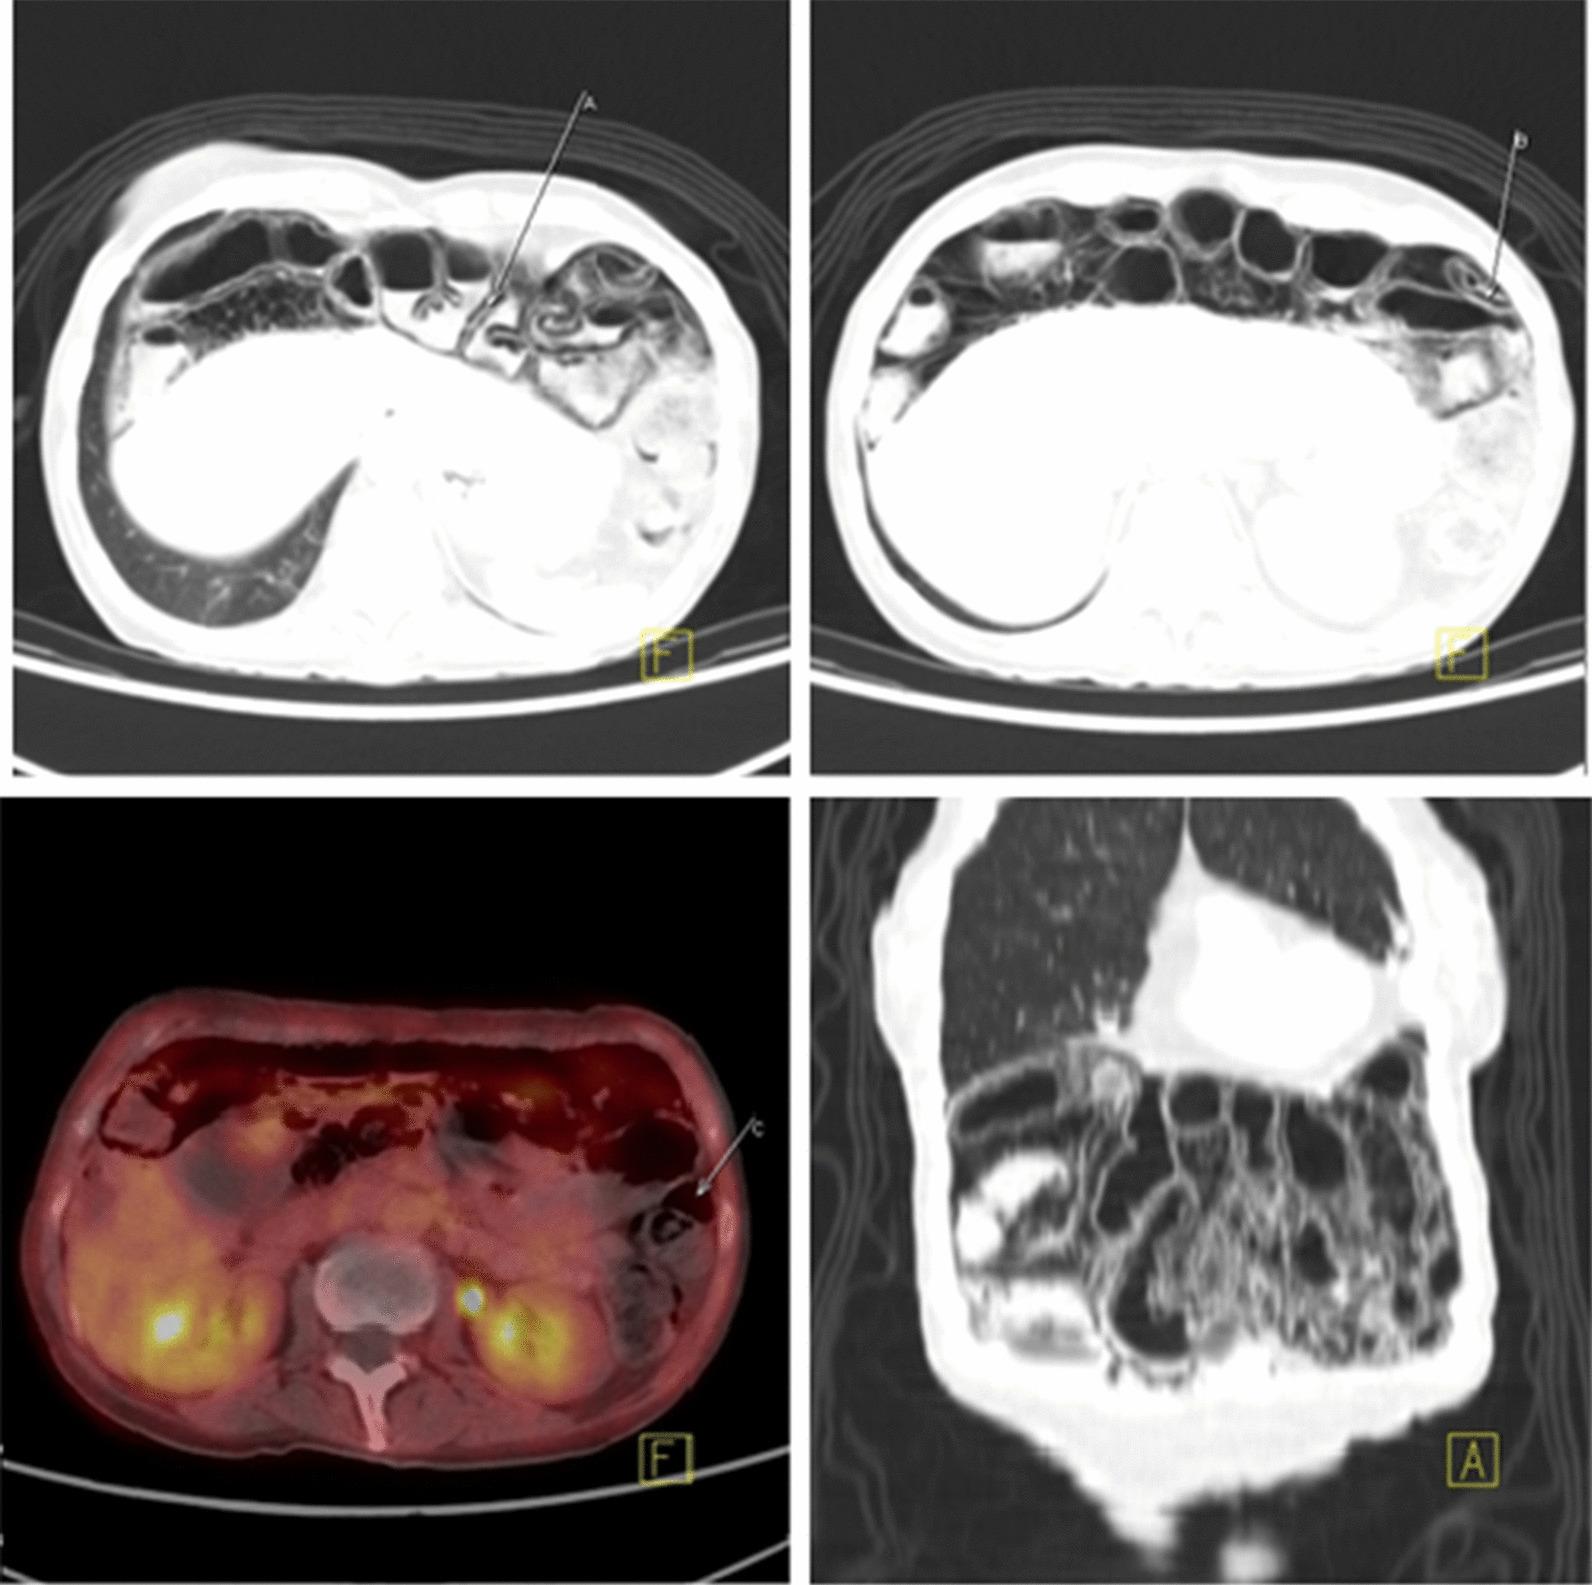

A 59-year-old caucasian female with radioactive iodine-refractory metastatic thyroid papillary carcinoma with BRAF mutation was treated with dabrafenib and trametinib as a compassionate use. After 4 months treatment, positron emission tomography-computed tomography (PET-CT) showed PI. At the time of diagnosis, the patient was asymptomatic without signs of peritonitis. The initial treatment was conservative and no specific treatment for PI was needed. Unfortunately, after dabrafenib-trametinib withdrawal, the patient developed tumor progression with significant clinical worsening.

一位 59 岁的白人女性,患有放射性碘难治性转移性甲状腺乳头状癌,BRAF 突变,接受了达布拉非尼和曲美替尼的同情治疗。治疗 4 个月后,正电子发射断层扫描-计算机断层扫描(PET-CT)显示有 PI。在诊断时,患者无症状,无腹膜炎迹象。初始治疗为保守治疗,无需针对 PI 的特殊治疗。不幸的是,在停用达布拉非尼-曲美替尼后,患者出现肿瘤进展,临床状况显著恶化。